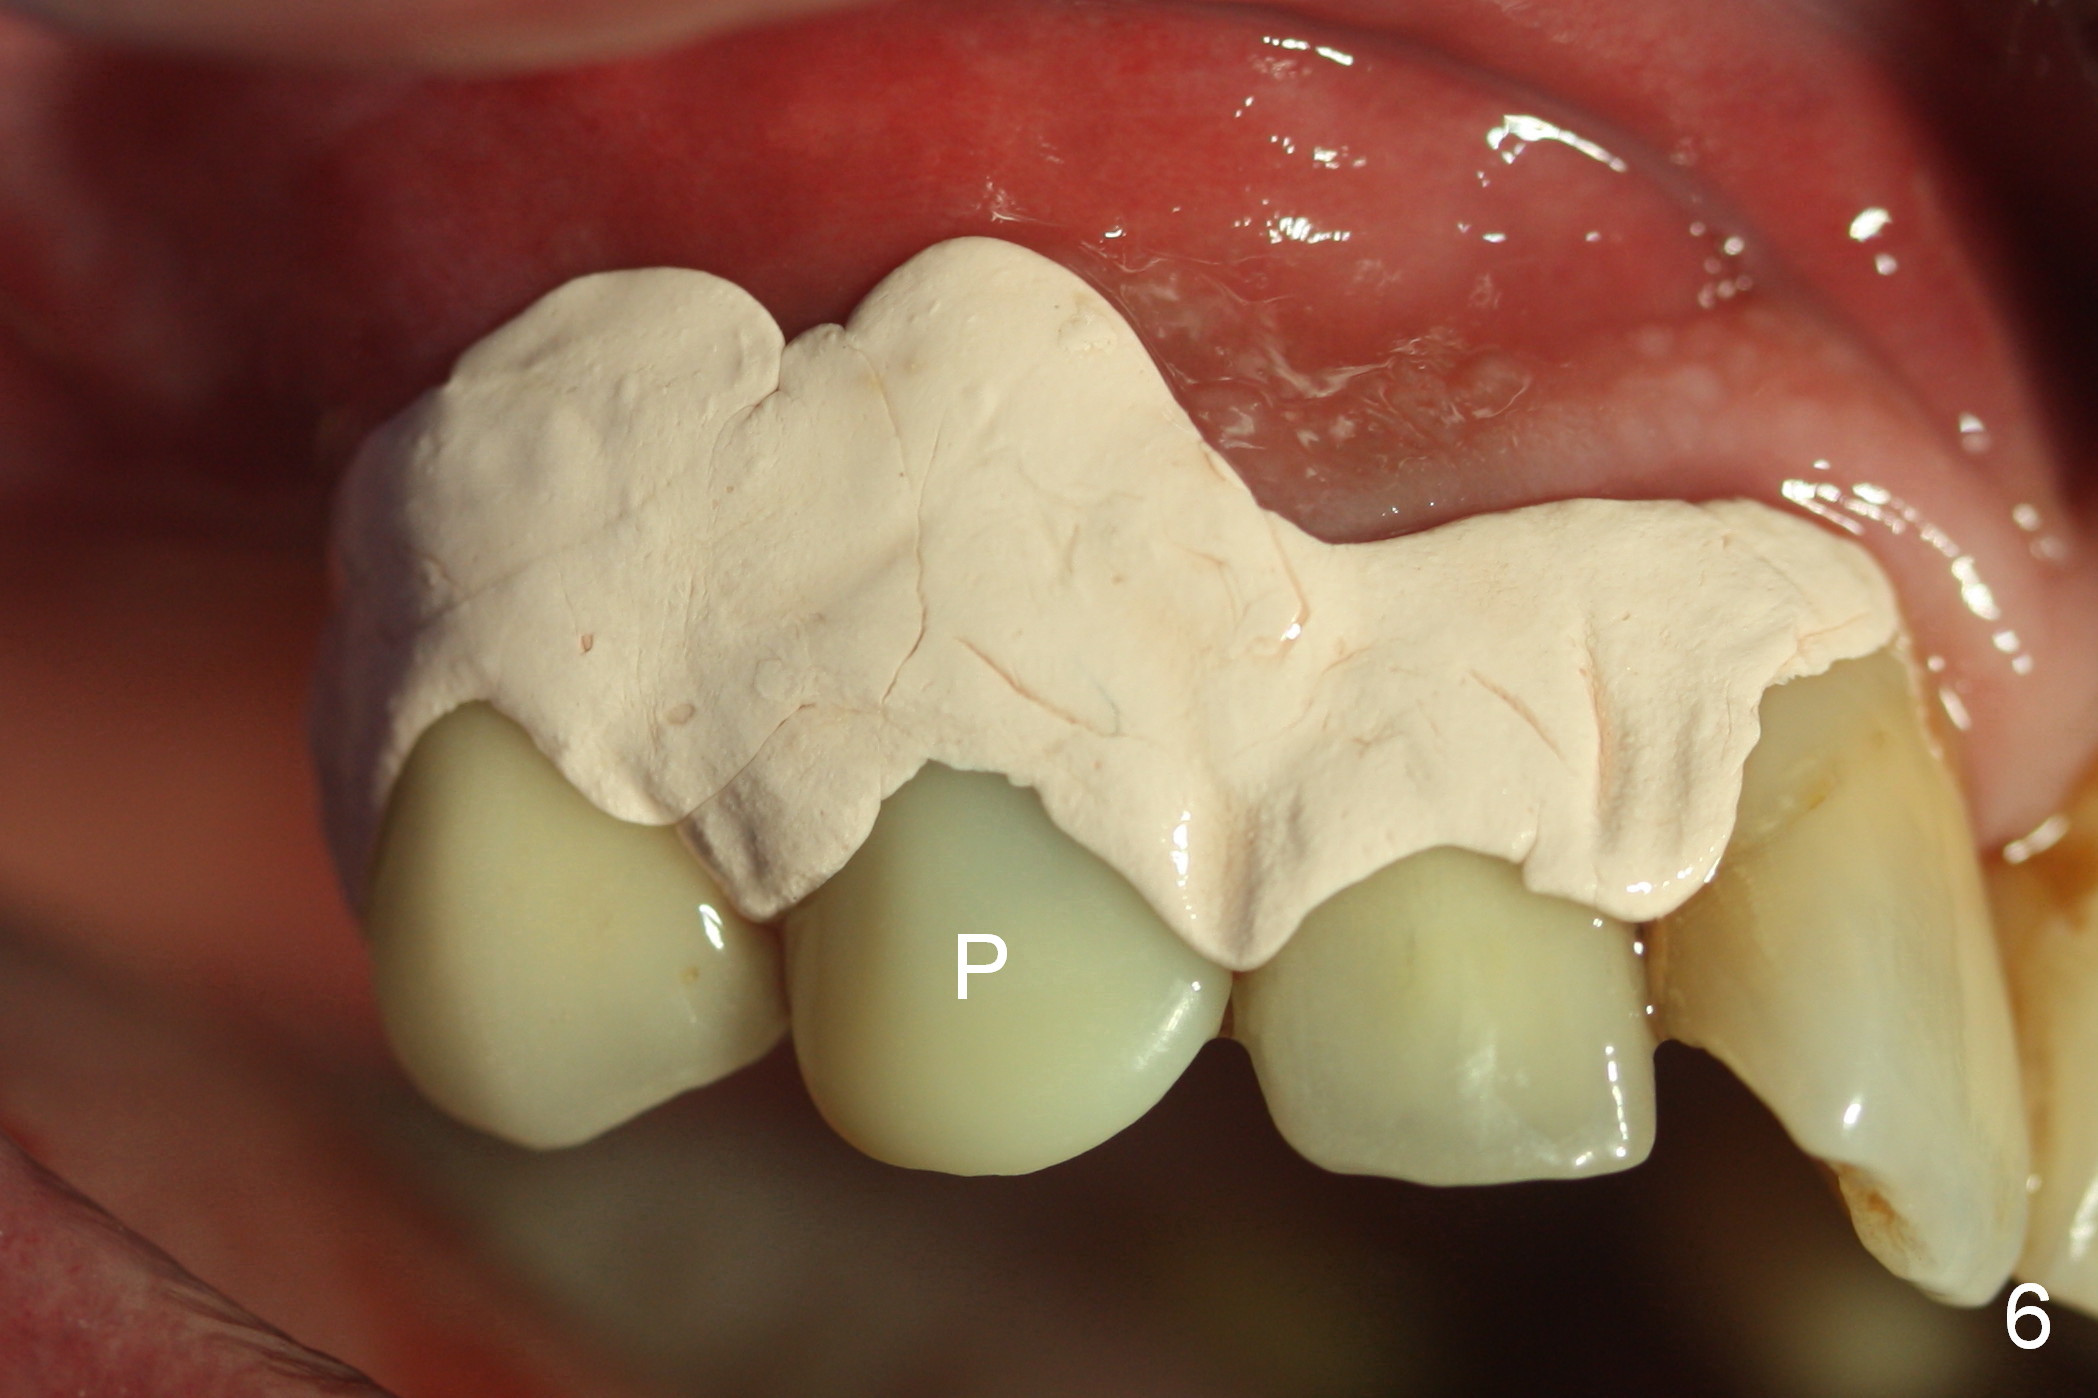

After extraction of the subgingival fractured upper right canine (Fig.1), the buccal plate is found to have been perforated at the apex. the root is measured 5x12 mm. Initial osteotomy with a 2 mm pilot drill shows that the bone is soft (Fig.2). After use of a 3.2 mm drill (underprep, normal drill size (3.7 mm)), a 4.5x15 mm implant is placed with insertion torque > 50 Ncm (Fig.3). The implant is further torqued until the implant plateau is 3 mm apical to the buccal gingival margin; a 5.5x5(3) mm abutment is placed (Fig.4,5 A). Osteogen plug is inserted into the apex of the socket, while the rest of gap is filled with mineralized cortical allograft and Osteogen. An immediate provisional (Fig.5,6 P) is fabricated to keep the graft in place, followed by periodontal dressing (Fig.6).